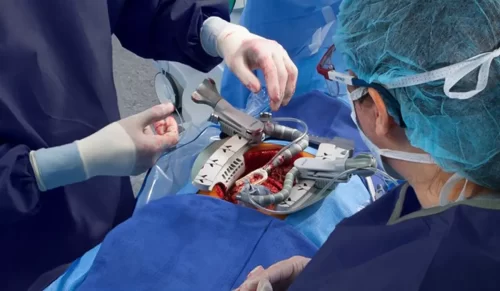

- جراحی بای پس کرونری

- جراحی دریچه قلب

- عمل پیشرفته و موفقیتآمیز تاوی (TAVI)در ایران، در شهر مقدس مشهد توسط دکتر سید محسن جهرمی مقدم